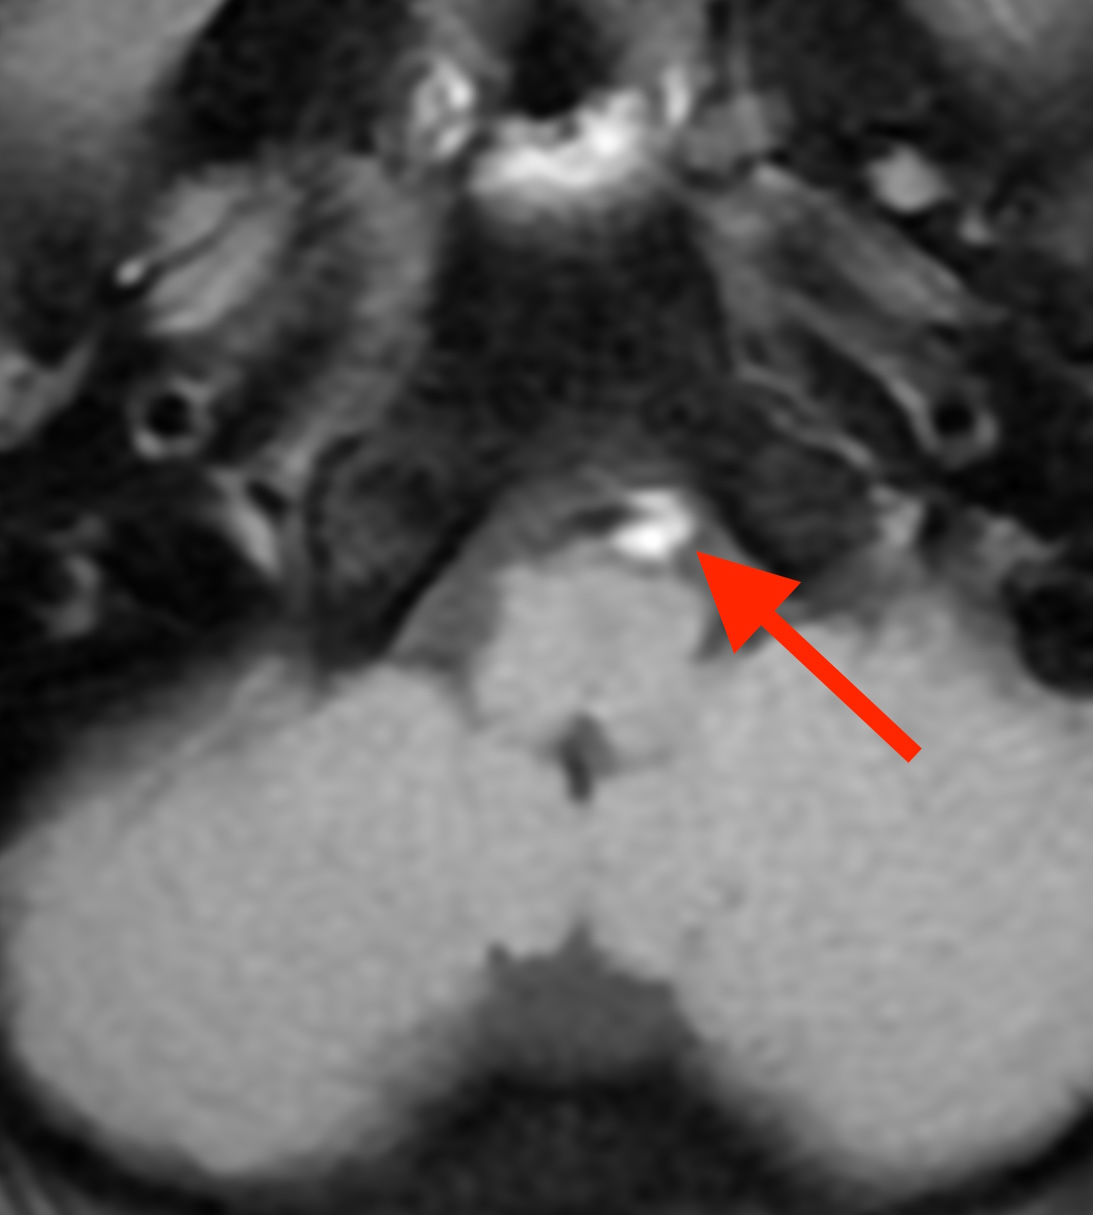

MRIで脳の血管を撮像しました。

右の首から後頭部へ行く椎骨動脈の一部がコブのように飛び出ています。

この部分をT1BB法(T1 black blood method)という特殊な撮像法で確認したところ、

血管内部が白く光って描かれています。これは血管内で血栓(血液の固まり)ができている事を意味します。

椎骨動脈解離という状態です。